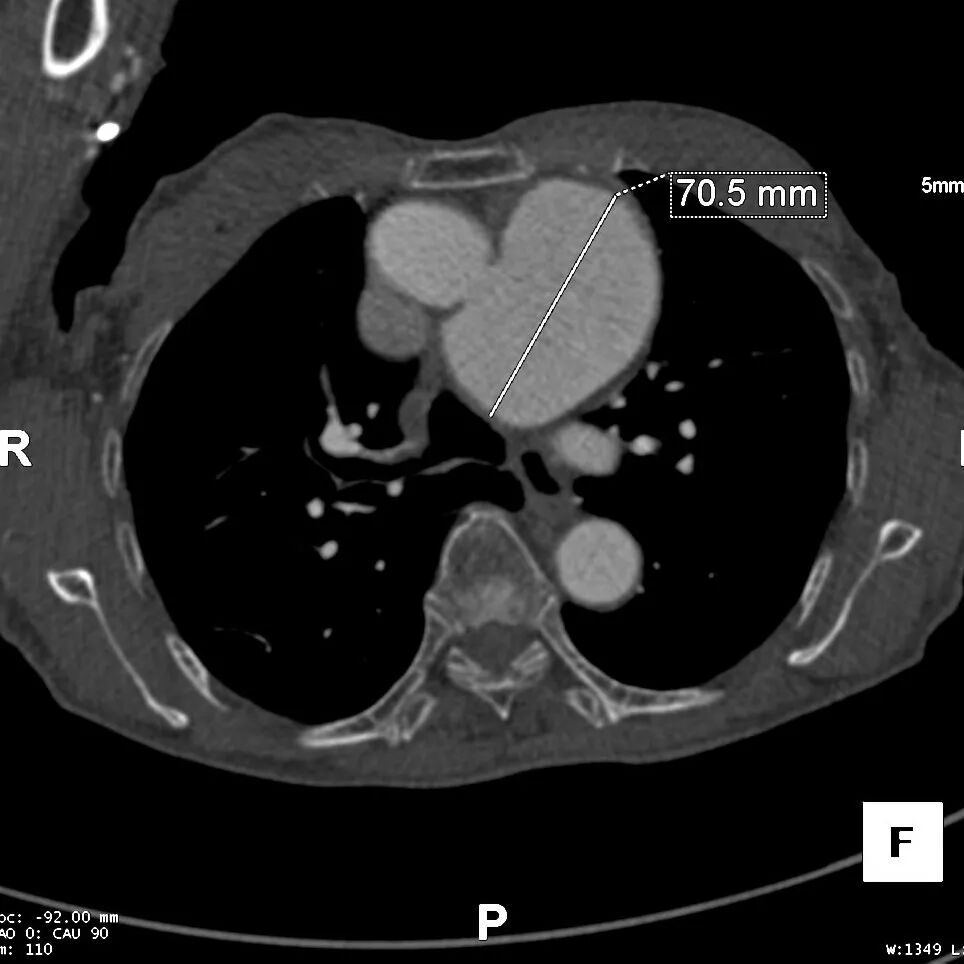

巨大胸主动脉瘤,直径70mm

病变累及LCCA附近,小弯侧锚定区长度11mm,非常极限